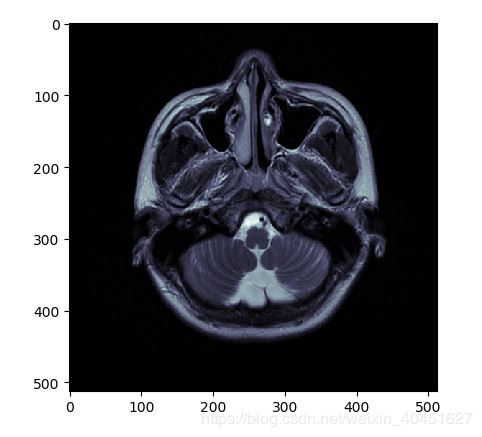

from matplotlib import pyplotpyplot.imshow(ds.pixel_array,cmap=pyplot.cm.bone)pyplot.show()

效果如图所示:

显然颜色是有区别的.导致这种差别的原因是pyplot函数使用的cm也就是'color map' 是简单的'bone' 并不能满足医学图像的要求.